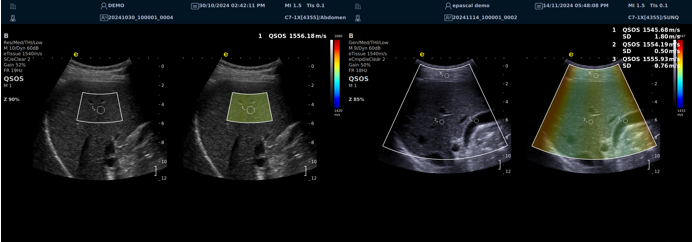

QSOS声速定量成像

测量原理

QSOS声速成像技术利用声波在组织中的传播速度差异性,计算不同位置的声速值,反映组织的物理特性。

成像过程

利用超声探头发射超声波脉冲,分析反射信号的时间延迟,确定声波传播路径和速度,构建声速分布图像。

图像显示

QSOS技术采用彩色编码显示声速图像,不同颜色代表不同声速值,便于医生识别病变部位和测量。

25fb8cb17586b86e5d915a2be3025a2.png

技术优势

?精准定量反映组织特性,成像更敏锐?彩色编码直观显示,轻松发现异常?捕捉声速差异,早期、微小病变更易察觉